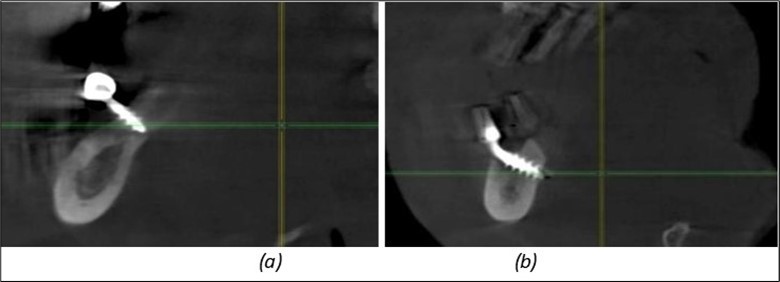

Figure 11.Implants in the anterior area anchored in the nasal cortex (BCS and TPG): (a), (c) – BCS implants fixed in the nasal cortex; (b), (d) – TPG implants fixed in the second nasal cortex with compression in the trabecular area.

Figure 12.Implants fixed distally in quadrant 4 with fixation at the level of the mylohyoid line: (a) The most distal implant fixed in unaffected bone from the previous restoration; (b) The implant fixed in the area where the two stage implant was removed.

Figure 13.Corticobasal BCS implants fixed between the vestibular and lingual cortices with support on the basal bone: (a) BCS fixed between the lateral cortices; (b) BCS implant with support on the basal cortex.